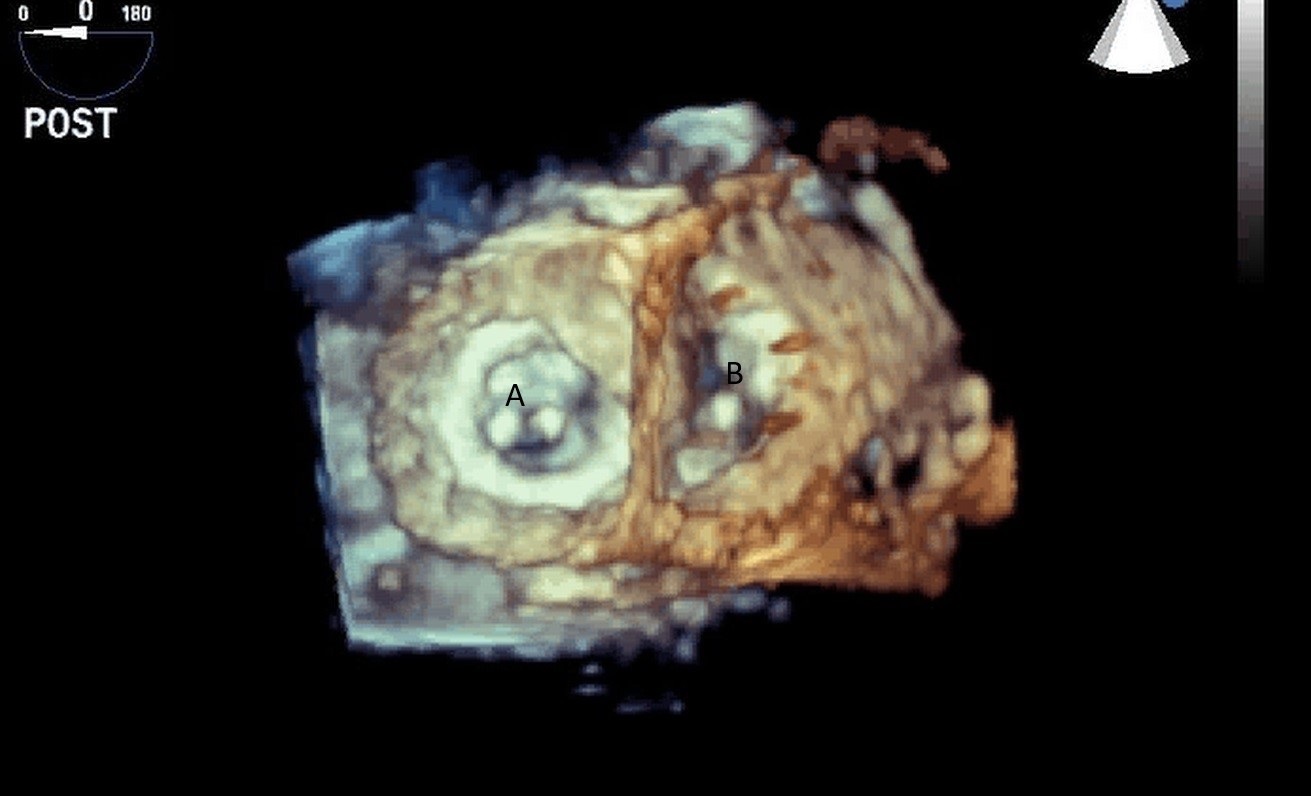

Both TTE and TEE can help with ideal positioning of the Impella (Figs. 5,6). The distance from the aortic valve to the Impella inlet should be measured. This should ideally be 3.5–4 cm for all Impella devices except for the Impella 5.5 for which it is 5 cm [15] (Fig. 7). The outlet should be 1.5–2 cm above the sinuses of Valsalva. The catheter should be angled towards the LV apex and away from the septum and mitral valve. The positioning of both the inlet in the LV cavity and the outlet above the aortic valve should be confirmed. Color flow doppler imaging can help confirm this positioning as a mosaic pattern will be visualized near the inlet and outlet ports on spectral doppler (Fig. 8). Real-time 3D echocardiography can also be used to help in visualizing Impella positioning relative to other anatomical structures (Fig. 9). After placement of the Impella, the aortic and mitral valves should be interrogated for any new or worsening regurgitation or dysfunction [16]. TEE can also help identify additional complications of Impella placement including pericardial effusion or LV free wall rupture [17].

Fig. 9.Real time 3D TEE imaging visualizing the Impella in relation to the aortic valve and LVOT. (A) Impella. (B) Ascending aortic root.